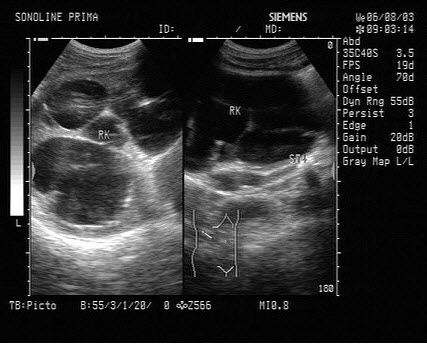

3、单项选择题

根据超声图像所示,判断致病人肾脏积水的梗阻在输尿管哪一段()

A.下段

B.中段

C.上段

D.膀胱内

E.肾盂内